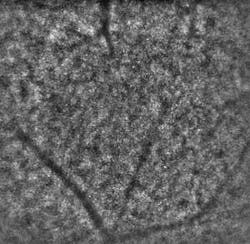

Just recently, the consortium delivered two of three planned prototypes of its Adaptive Optics Flood Illumination Fundus Camera (AO FIFC) for field tests to evaluate their potential for clinical investigations. Initial feedback from the consortium’s medical partners has been positive. “When the first INOVEO prototype reached our hospital, we were immediately startled by its compact size, similar to that of a standard retinal camera,” notes Olivier Roch, MD, at the Hôpital Necker, a children’s hospital in Paris. “While the adaptive-optics systems that we had previously seen in various publications seemed to occupy the surface of a very large desk, the new prototype fit perfectly into our clinical setting. After just a couple of days of training, our medical researchers were able to immediately proceed with the project’s clinical investigation program. The first cellular-resolution images revealed an impressive level of detail that could never have been seen with conventional imaging instruments.”

“The AO FIFC’s high resolution and relatively wide field of view make it an invaluable device for diagnosing macular holes when conventional imaging techniques are unable to confirm the patient’s subjectively reported visual symptoms,” notes Kiyoko Nakashima, MD, from the Hôpital Necker. The macula is responsible for our detailed, sharp vision and, at the early stages of this disorder, changes in visual acuity often occur or straight lines may appear wavy. Because the AO FIFC enables doctors to assess the presence and function of photoreceptors around the macular hole and monitor its two-dimensional progression, this may help them to decide whether a natural regression is likely or if a surgical intervention is required.